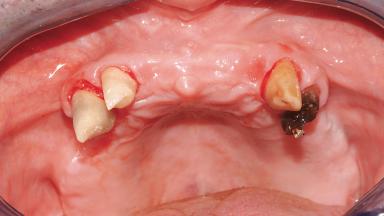

Immediate Loading of Six Implants in the Maxilla and Final Restoration with a Full-Arch Gold/Ceramic FDP Involving the Concept of Tilted Implants

A 61-year-old male patient with a failing fixed maxillary rehabilitation and a fixed mandibular rehabilitation requested a new fixed maxillary rehabilitation. The patient was wearing a temporary metal-reinforced maxillary bridge inserted two years before the consultation. He reported that his previous dentist did not want to insert a definitive framework because he considered the residual teeth to have a negative prognosis. The patient reported a history of recurrent caries and endodontic complications as the main reason for the previous extractions. The anamnesis was negative for periodontal disease and bruxism. The patient’s chief compliant was the mobility of his maxillary prosthesis, which needed to be re-cemented frequently, and discomfort during chewing.Moreover, the patient was not satisfied with the esthetic appearance of his maxillary teeth, which he found too long. The patient asked for a stable and comfortable fixed maxillary rehabilitation and firmly rejected any removable solution.

Case Type Edentulous Maxilla

# of Teeth All